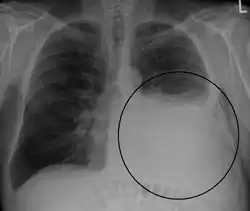

Op een longfoto is pleuravocht zichtbaar als een wit gedeelte op de longfoto.[4] Op een normale thorax foto is de ruimte tussen de viscerale pleura en de pariëtale pleura niet zichtbaar. Wanneer er pleuravocht aanwezig is, is deze ruimte wel zichtbaar. De densiteit van pleuravocht is ongeveer gelijk aan die van water, hierdoor is dit witter op een longfoto in vergelijking met de rest van de long (die meer de densiteit van lucht heeft). Door de hogere densiteit zal pleuravocht zich altijd bevinden op het laagste punt van de thoraxholte en is er een bij horizontale vloeistofspiegel (meniscus).[5] Een longfoto in zijligging (op de zijde waar het pleuravocht zich bevindt) is sensitiever voor pleuravocht. Dit wordt een "decubitus opname" genoemd, bij deze opname wordt een hoeveelheid van 50 ml of meer pleuravocht zichtbaar. Een CT-scan van de borstkas is het meest nauwkeurig voor het bepalen van de aanwezigheid van pleuravocht, maar ook de hoeveelheid en kenmerken van het pleuravocht. Ook echografie kan gebruikt worden om pleuravocht aan te tonen.[6]

Forse hoeveelheid pleuravocht links bij een patiënt met longkanker.